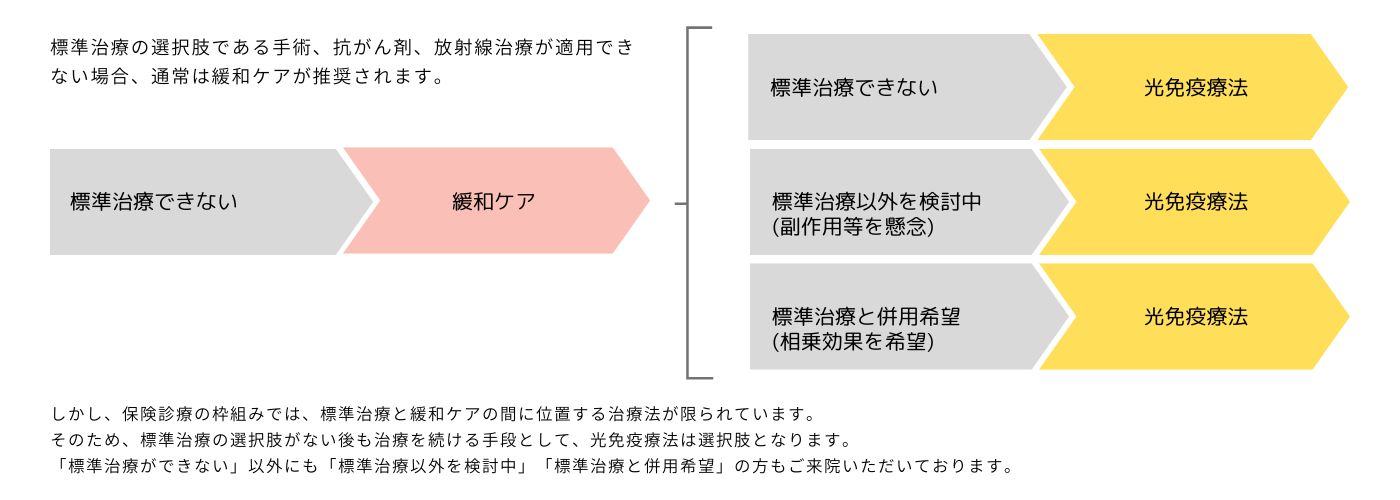

光免疫療法の主な位置づけ

Positioning of PDT

光免疫療法の特徴

Features of PTD

併用できる治療

他の治療との併用が可能です。標準治療はがん治療において非常に効果的ですが、治療法ごとに適用範囲や強みが異なることも事実です。それぞれの治療法の相乗効果を期待し、複合的な治療を提供することも可能です。

効果を向上させる複合治療

- 光免疫療法による腫瘍細胞の死と抗原の放出は、免疫システムを「目覚めさせる」効果があります。これにより、通常は「見過ごされがち」な腫瘍細胞に対する免疫システムの識別能力が向上します。

- PD-1阻害剤による介入は、この「目覚めた」免疫応答が腫瘍細胞に作用するための障害を取り除きます。つまり、光免疫療法で活性化された免疫応答が、PD-1阻害剤によりさらに強化され、効率的に腫瘍を攻撃することができるようになります。

これらの理由から、光免疫療法とPD-1阻害剤は組み合わせて使用すると、単独で使用する場合に比べて腫瘍に対する攻撃力が強化される可能性があります。

標準治療との併用は可能です。標準治療と併用する事で双方に良い相乗効果が期待出来ます。現在通われている病院の治療のご予定を確認させて頂きながら当院の治療スケジュールを組ませて頂きますのでご安心して通っていただけます。